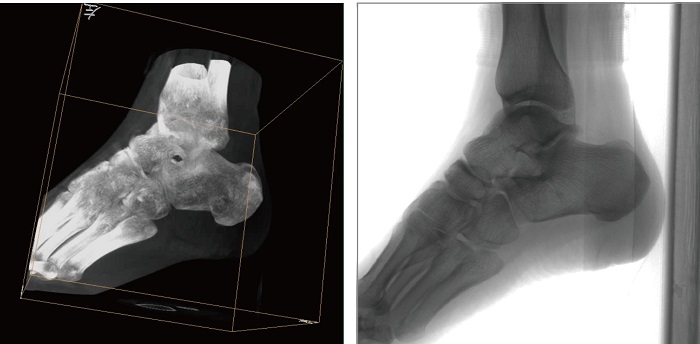

1、術中三維成像。PLX C7500A三維C型臂的術中三維成像和類CT切片圖像提供更全面的手術診斷信息,輔助醫生進行術中準確評估判斷諸如骨折復位情況和內植入螺釘的尺寸和位置,保證了手術高精度地完成。

2、動態平板探測器。PLX C7500A三維平板C臂機采用30cmx30cm的動態平板探測器,輸出高分辨率、大尺寸的二維、三維圖像。達到16比特灰階度,高動態范圍清晰顯示植入物的位置和輪廓。

3、穩定全面的圖形采集。PLX C7500A三維平板C形臂具有等中心掃描技術,始終保持拍攝主體處于射線束的中心,避免C臂機架的橫縱方向的運動,從根源上減少了運動偽影了產生,提升圖像的清晰度。同時可190°三維采集角度,電驅動沿軌道滑轉,提供高精度、全方位的三維圖像及類CT切片圖像信息。